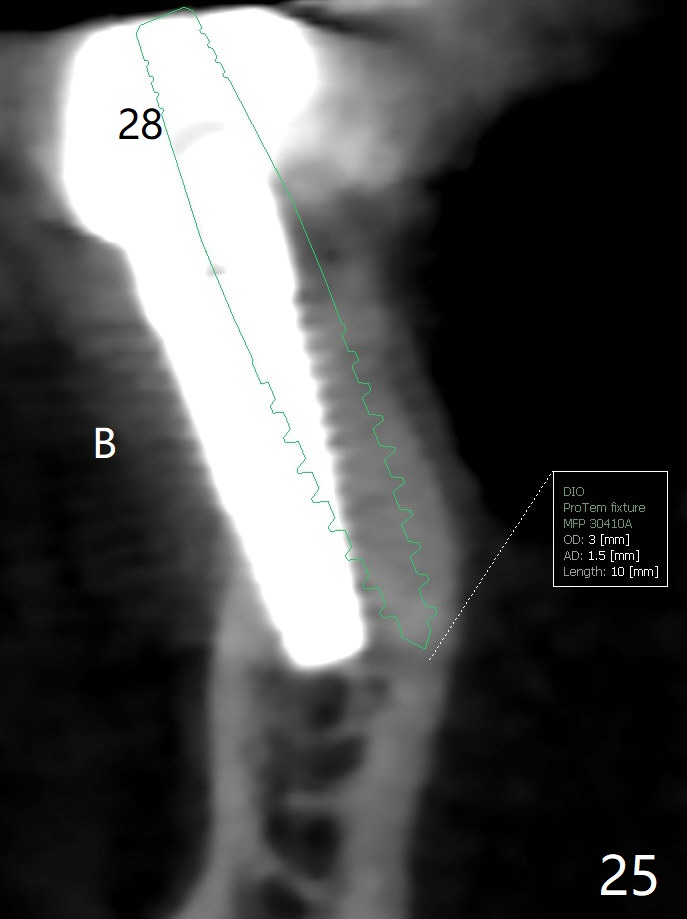

Two of 2.5 mm 1-Piece Implants M

The edentulous ridge at #30 is narrow (Fig.1). After ridge reduction, osteotomy is initiated with 1.2 mm drill for 10 mm; the mesial osteotomy is to be changed (Fig.2 red line). Using a 1.2 mm drill placed in the distal osteotomy (Fig.3 D), the mesial osteotomy changes in trajectory with subsequent placement of a 2.5x10(4) mm 1-piece implant. Since the mesial implant is high in occlusion, the cuff of the distal implant is changed to be 2 mm (Fig.4 (shorter black line)). Panoramic X-ray is taken to show no violation of the Inferior Alveolar Canal (Fig.5 red dashed line). These two 1-piece implants are slightly lingually placed (Fig.6). The crestal bone around the implants resorbs without thread exposure 5 months postop (Fig.7). Impression is taken for a splinted crown (Fig.8-12). There is no metal show around the 2.5 mm 1-piece implants 6 months postop (advantage) vs. that at #28 and 29 (Fig.13). Bitewing is taken post cementation to determine whether residual cement is present (Fig.14). There is periodic swelling and pain in the lower right quadrant 2 years post cementation (Fig.15). In fact periimplantitis appears to have developed at #28 (Fig.16) with loss of the buccal bone (Fig.17,18). The buccal bone loss is less at #29 (Fig.19) and #20 (Fig.23) and no at #30 mesial and distal implants (Fig.20,21). A much smaller implant will be placed lingually at #28 immediate (Fig.24,25).